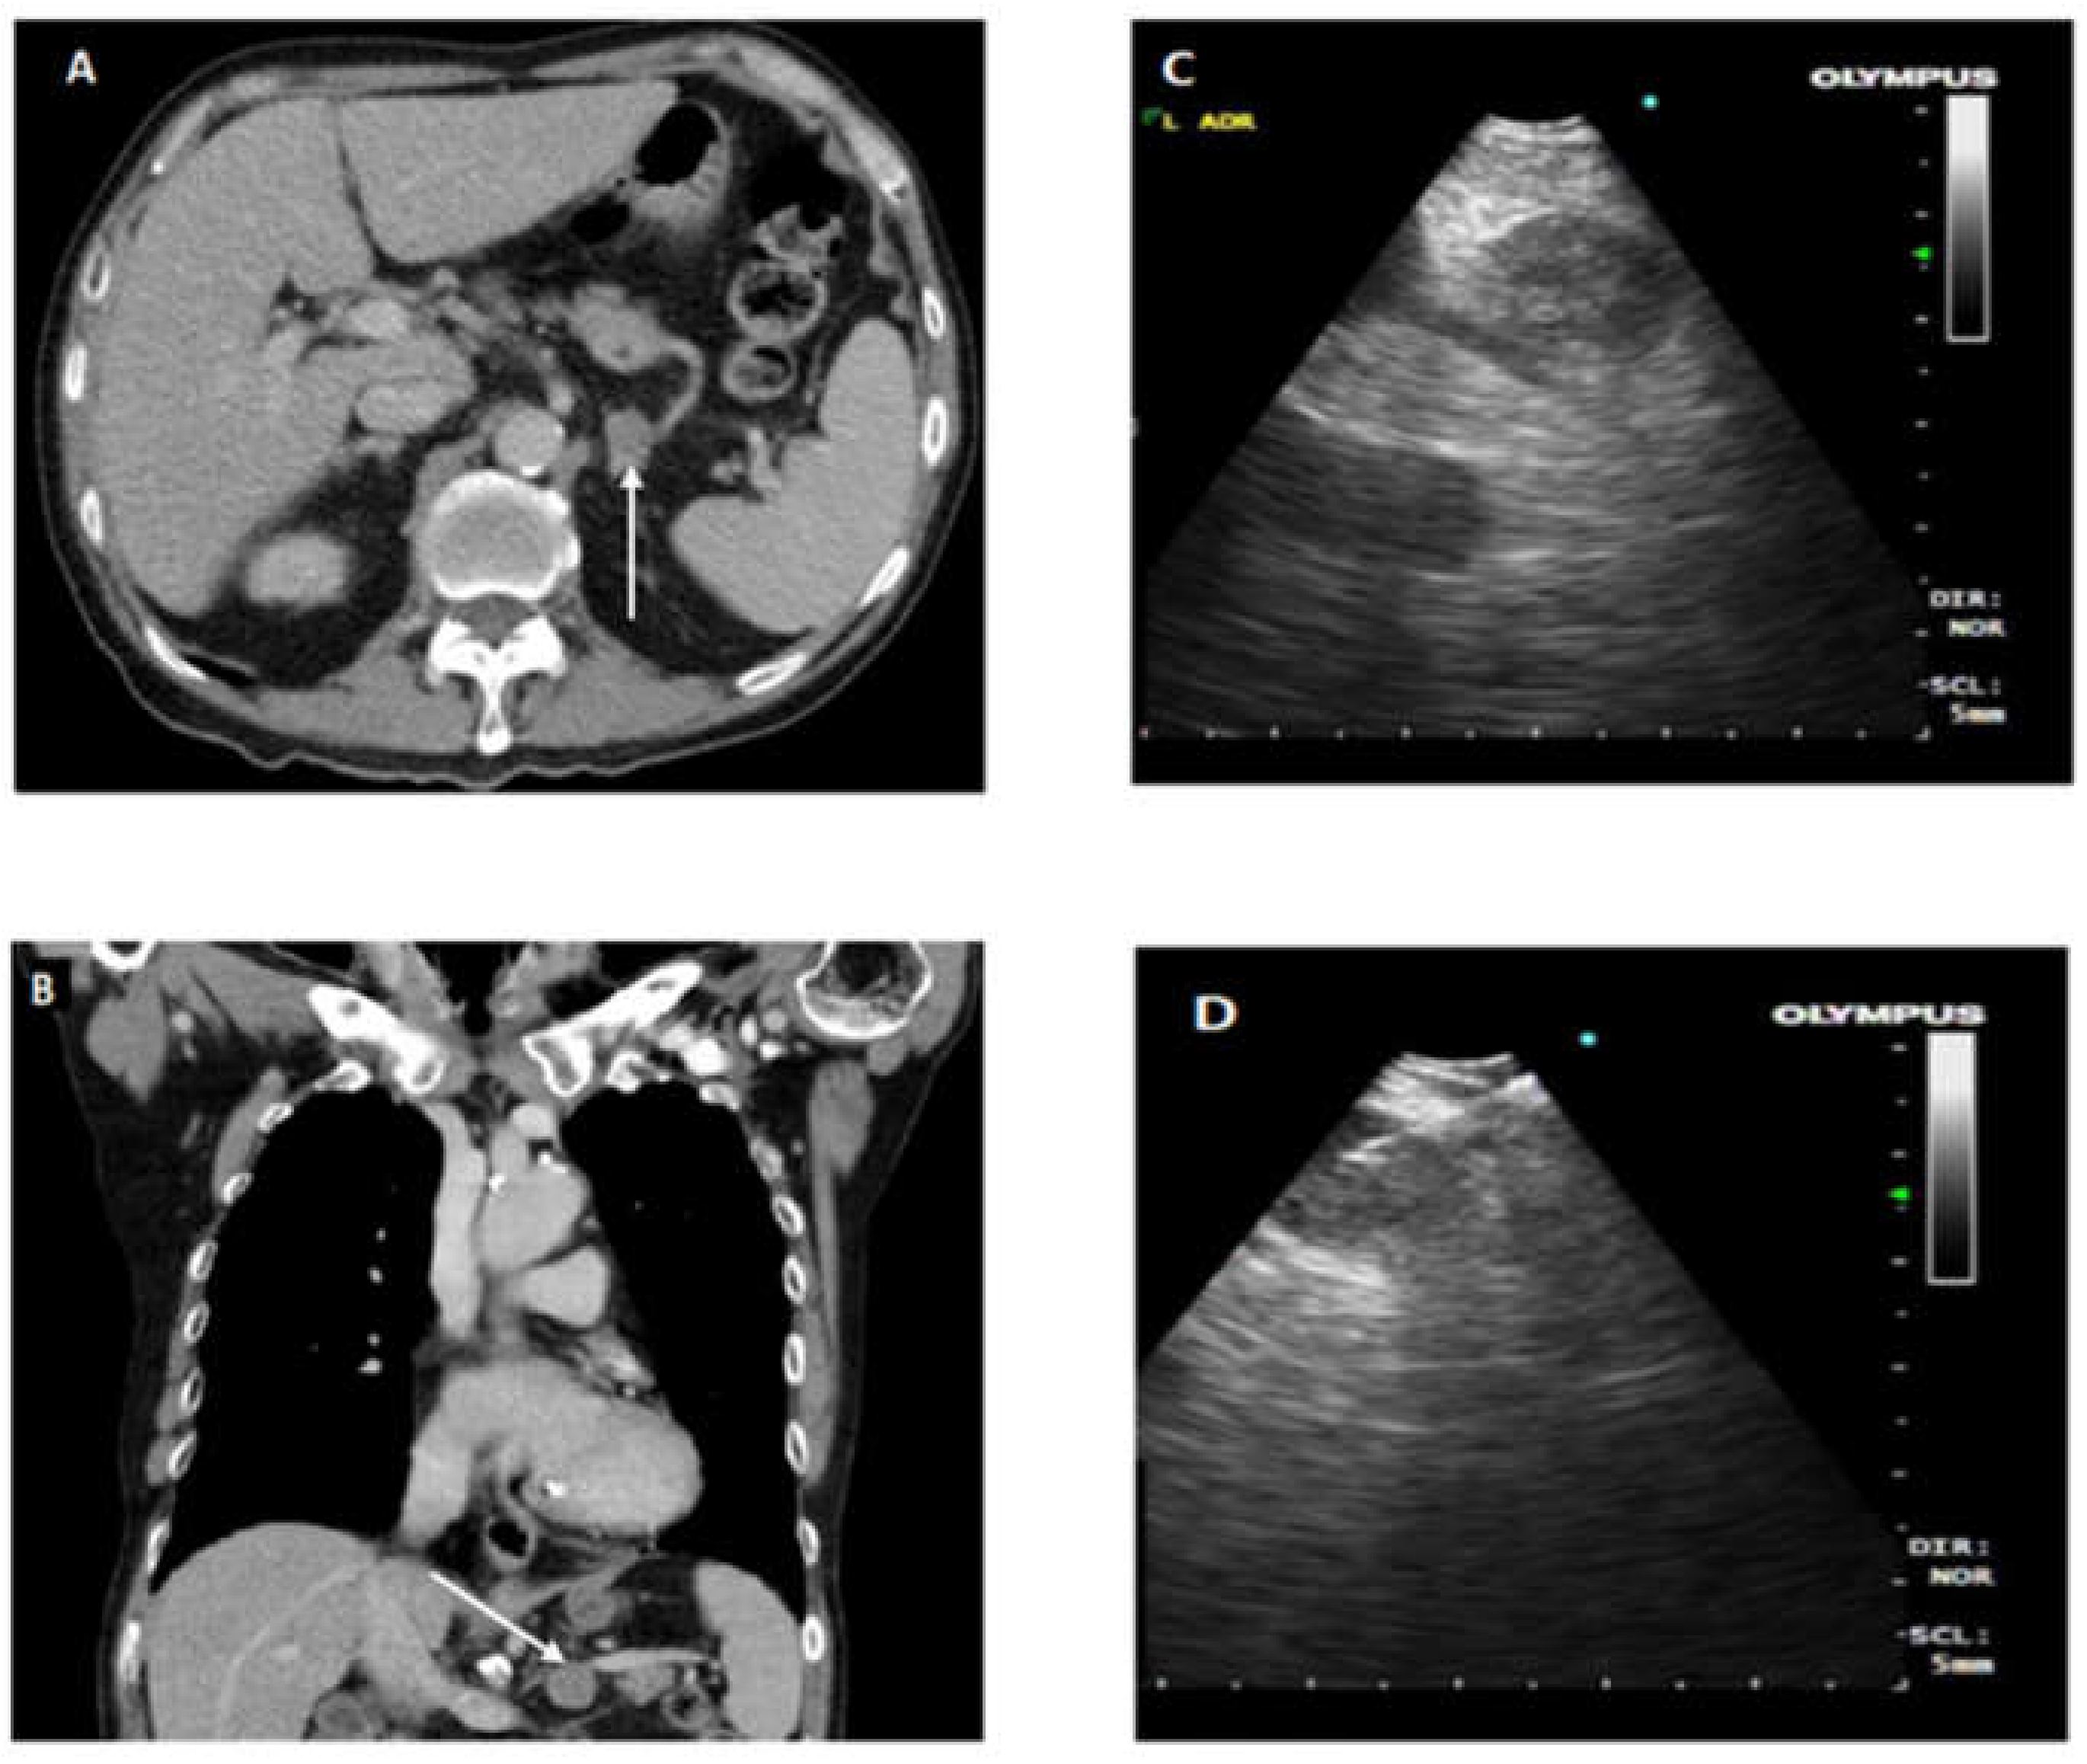

Cases that required EUS-B FNA after EBUS assessment or were assessed to require only EUS-B FNA had standardized EUS-B procedure as described previously [3,4]. EUS-B was introduced into esophagus by mouth and oropharynx. In accordance with EUSAT assessment method described by Konge et al. [10], the order of identification of landmark is as follows: liver, adrenals, coeliac axis, station 7, and then station 4 left. Needle sheath is pushed out and visualized before puncturing the lymph node under ultrasonic visualization. After removal of stylet, multiple needle aspirations are made. Needle is fully retracted before removal from EBUS scope for specimen collection. To prevent upstaging of lung cancer, all FNA biopsies were done in following order of M1 distant metastases followed by N3, N2, and N1. Ultrasound images of lymph node stations and fine needle aspirate of lymph nodes are recorded and kept in patient electronic records. Close attention and supervision are given to needle handling for assurance of patient and equipment safety. Figure 1. provides CT and endoscopic ultrasound images for illustration of EUS-B FNA.

Figure 1.

(A,B) CT axial and coronal sections, respectively. Arrowhead indicates enlarged left adrenal gland (LAG); (C) demonstrates EUS-B image of LAG; (D) illustrates EUS-B FNA of enlarged LAG with needle in target lesion.